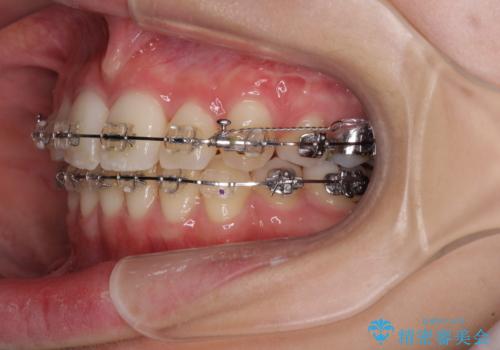

治療途中で転院 抜歯矯正の仕上げ治療

- 地元で抜歯治療を行っている途中、東京へ転職したため治療を継続して欲しいとのことで来院された患者様です。

出っ歯を抜歯矯正にて治療をしていらっしゃいましたが、抜歯スペースが少し残っていたため、閉じて歯列を仕上げていくこととしました。